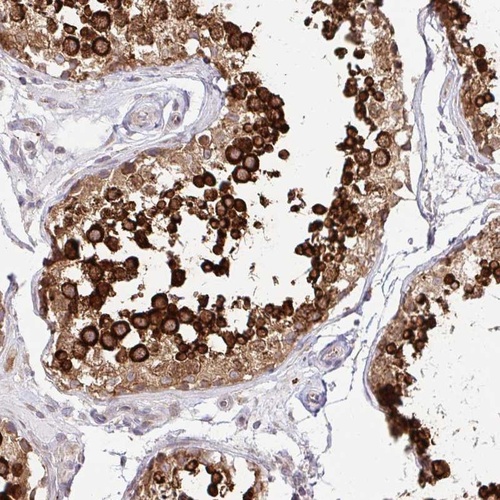

Immunohistochemical staining of human testis shows strong cytoplasmic positivity in cells in seminiferus ducts.